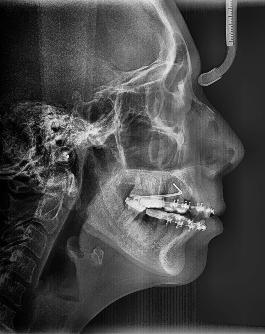

Estudios radiográficos de inicio

En la radiografía lateral de cráneo (Figura 4) se ve la aparatología con la que llegó la paciente, el perfil es convexo, hiperdivergente y las vías aéreas permeables.

Figura 3. Oclusal superior e inferior. Figura 4. Radiografía lateral de cráneo de inicio.